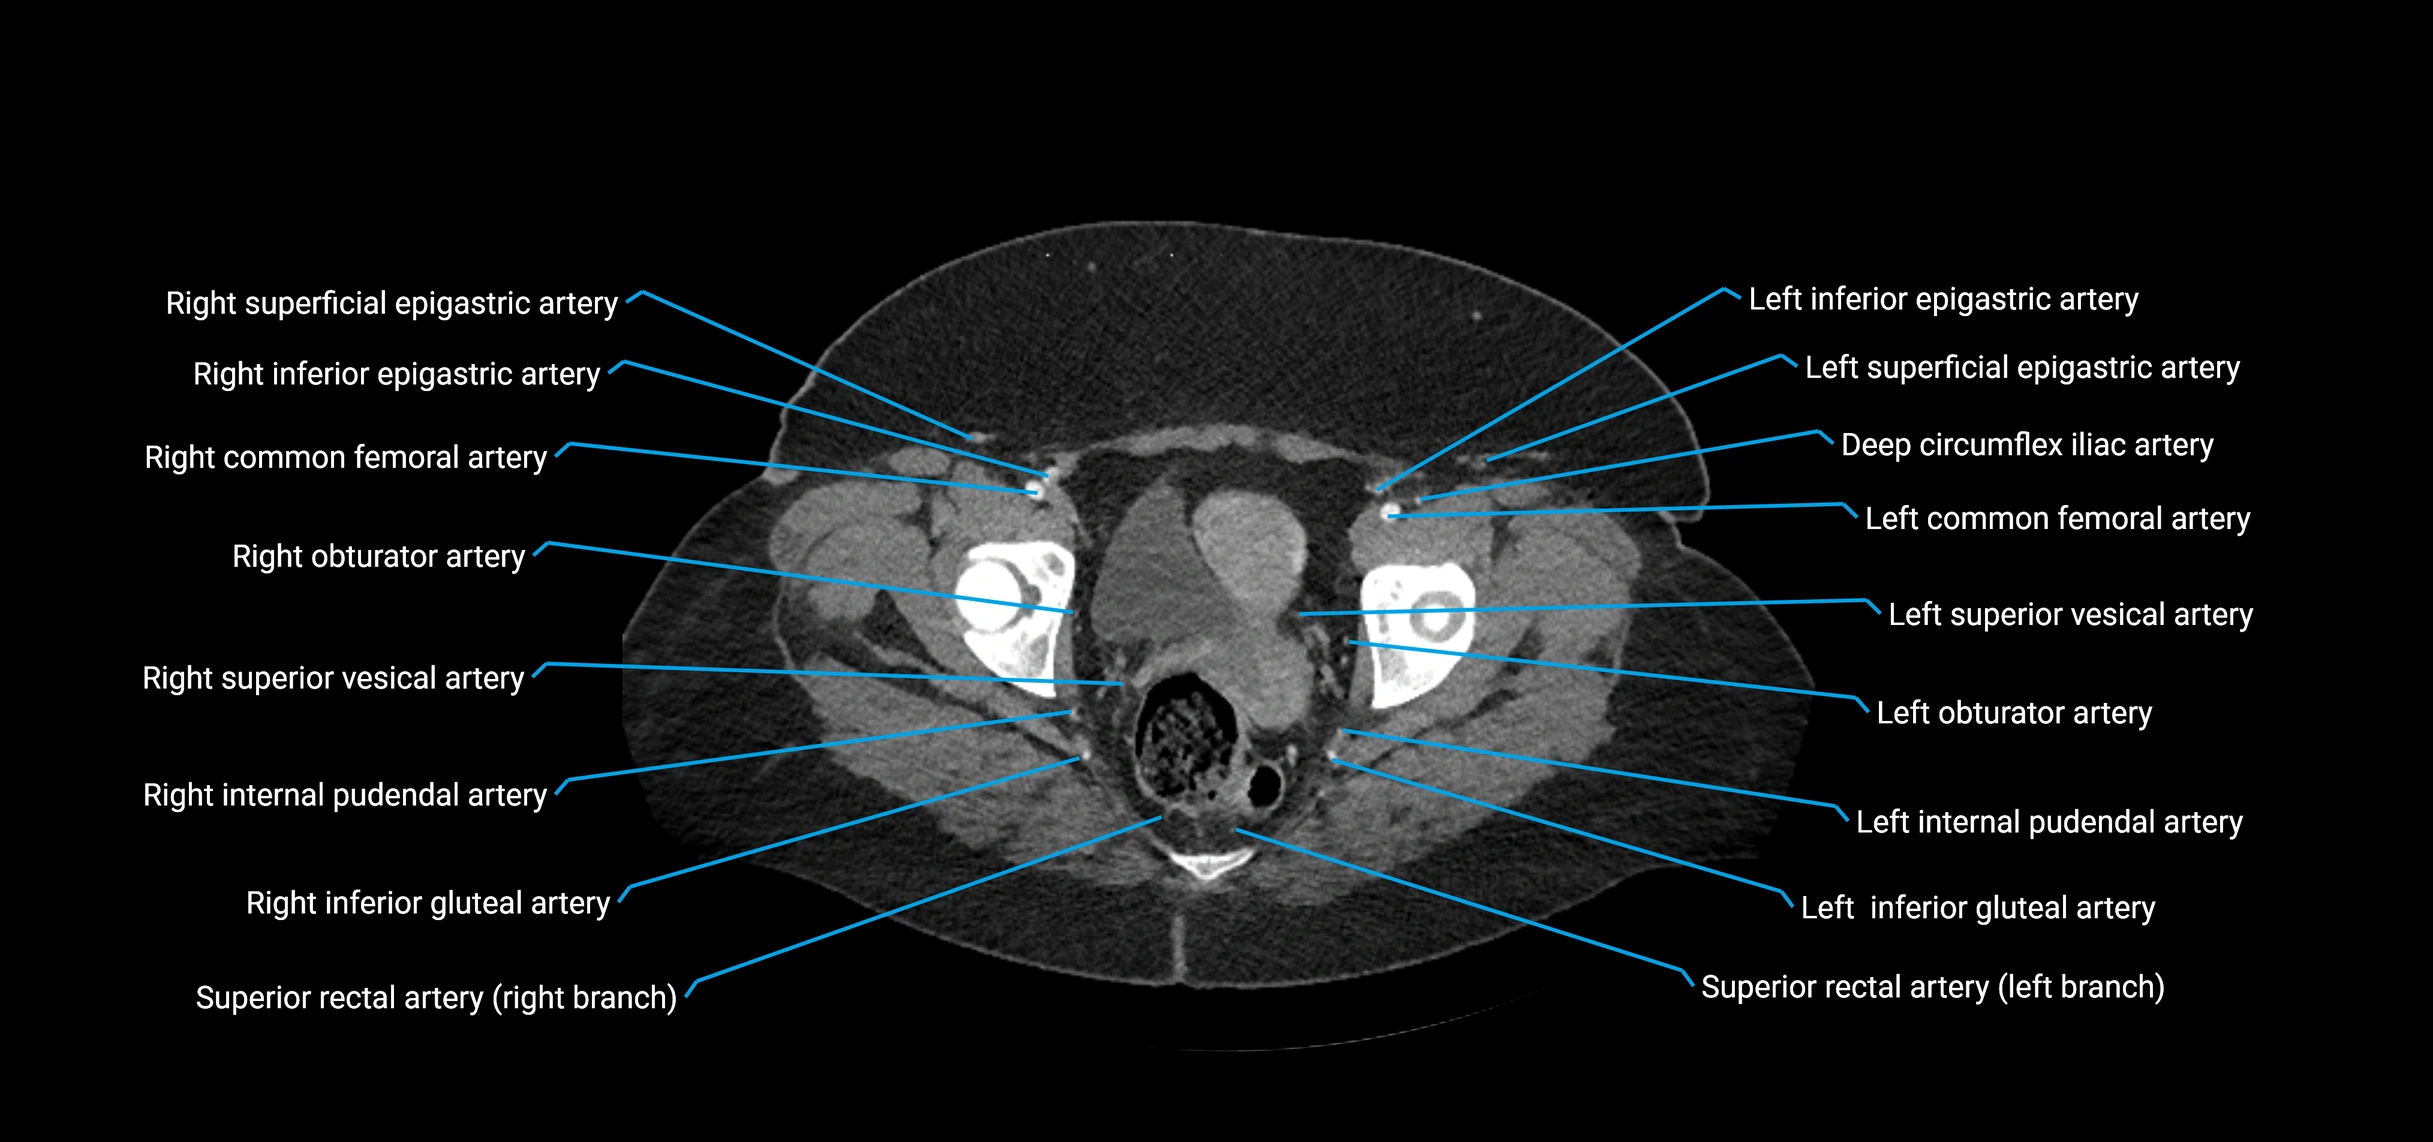

CT Appearance

Contrast-enhanced CT (CTA):

• Gold standard for abdominal aortic imaging

• Provides excellent detail of lumen, wall, aneurysm, thrombus, and branch vessels

• Multiplanar and 3D reconstructions help in aneurysm measurement, stent graft planning, and dissection evaluation

CT images

image